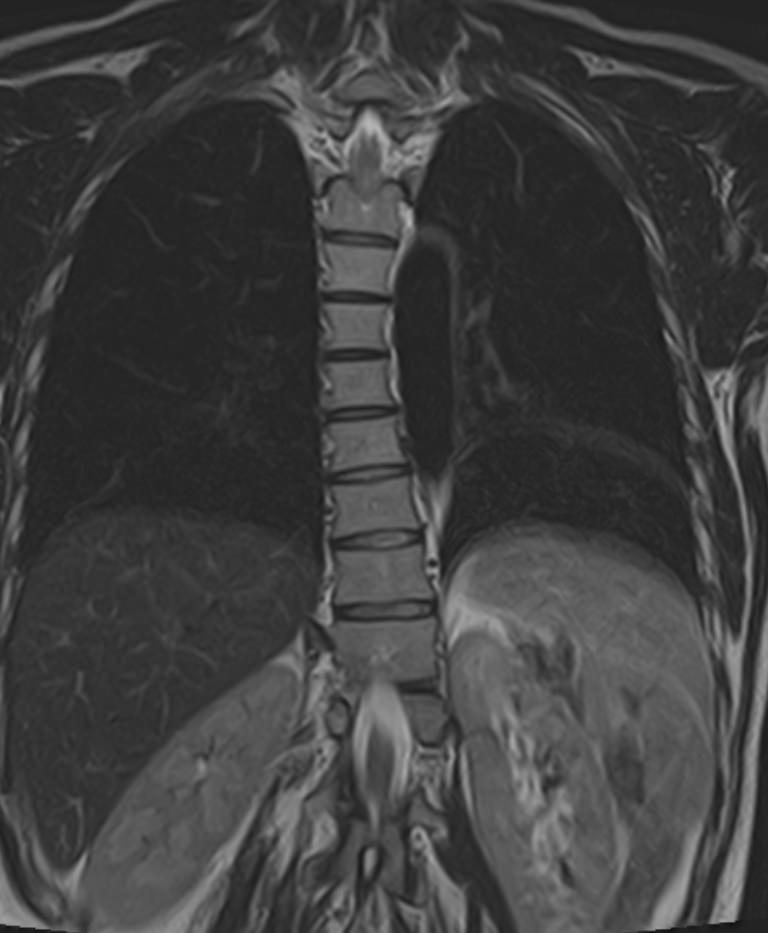

МРТ является современным высокоточным исследованием грудного отдела позвоночника, с помощью которого можно диагностировать различные заболевания, в том числе воспалительные, дегенеративные и опухолевые процессы. Преимуществом данного метода является его безопасность (отсутствие рентгеновского излучения), безболезненность, неинвазивность, при этом высокая информативность.

Клиника «Доступная медицина» оснащена новейшим томографом экспертного класса TOSHIBA VANTAGE TITAN 1,5 Тесла, который позволяет получать превосходные изображения с мельчайшей детализацией всех структур исследуемой области. Это позволяет ставить точный диагноз и выявлять различные заболевания позвоночника на самой ранней стадии.

С помощью МРТ грудного отдела выявляют следующие заболевания позвоночника:

• новообразования;

• степень повреждения спинного мозга в случае переломов тел позвонков;

• грыжи Шморля;

• травматические повреждения тел позвонков и остистых отростков (трещины, переломы, смещения и пр.) — при недоступности КТ;

• разрывы, растяжения связок;

• травмы спинного мозга, нервных корешков;

• протрузии;

• грыжи межпозвонковых дисков;

• остеохондроз позвоночника;

• стеноз спинномозгового канала;

• сосудистые патологии;

• остеомиелит, спондилодисцит;

• рассеянный склероз;

• спондилоартроз;

• спондилез.